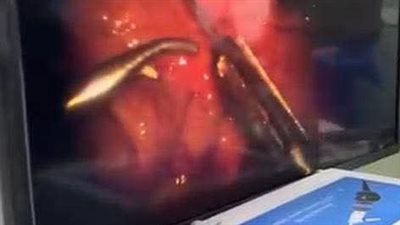

بعد 13 عامًا من أول عملية.. جامعة بني سويف تجري عملية تغيير الصمام الأورطي عبر القسطرة TAVI

نجاح إجراء عمليتين جراحيتين معقدتين بمستشفى دكرنس العام باستخدام جهاز C-ARM

مستشفيات جامعة المنوفية تُجري أول عملية قسطرة مخية بنجاح وتنقذ مريضًا من خطر النزيف الدماغي